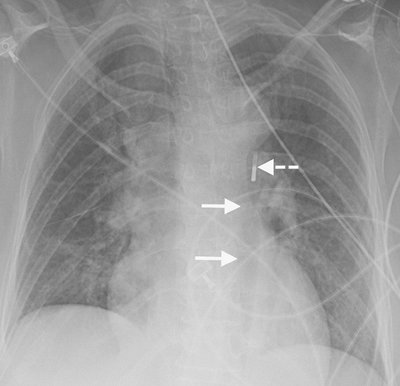

Numerous types of single- and dual-lead pacemakers and combination pacer–defibrillators are available. They are used to treat a variety of dysrhythmias. Accurate interpretation of their appearance on chest radiography requires knowledge of the specific type of pacemaker placed. The three major approaches to insertion of a pacemaker electrode into the heart include epicardial, subxiphoid, and transvenous implantations; transvenous is the most common. With single-lead pacers, the wire is placed into the right ventricle by way of the cephalic, subclavian, or jugular vein. When the lead is wedged into the myocardial trabeculae near the cardiac apex, the lead will be stable and have maximal contact with the endocardial surface. With dual-lead pacers, one lead is generally placed into the right atrium and the other into the right ventricle. It is important to know where the desired placement of leads is for each patient, because placement within the coronary sinus may be accidental or purposeful. After the electrodes are positioned, the generator is placed in a pouch in the subcutaneous tissues of the chest wall or beneath the pectoralis muscle. Biventricular pacemakers are used to treat congestive heart failure. Leads are placed in the right atrium and right ventricle, and a third lead is placed in the coronary sinus for pacing the left ventricle (Fig. 5-18).

FIGURE 5-18. Biventricular pacer. PA (A) and lateral (B) chest radiographs show normal positioning of lead tips in the right atrium (solid white arrow), right ventricle (dashed white arrow), and coronary sinus (solid black arrow).